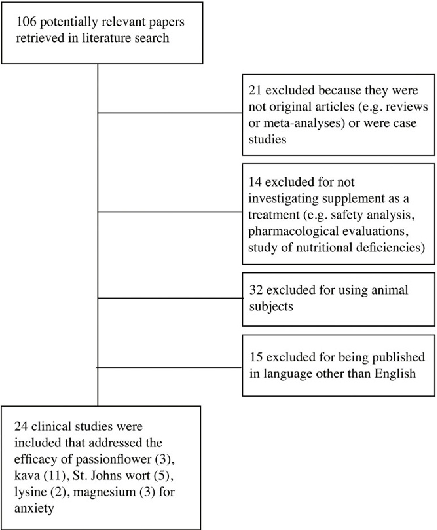

A PRISMA flow diagram outlines the systematic search and screening process for studies evaluating nutritional and herbal supplements for anxiety disorders. Database searches, inclusion criteria application, and final study selection are detailed.

Nutritional and herbal supplements for anxiety and anxiety-related disorders: systematic review.